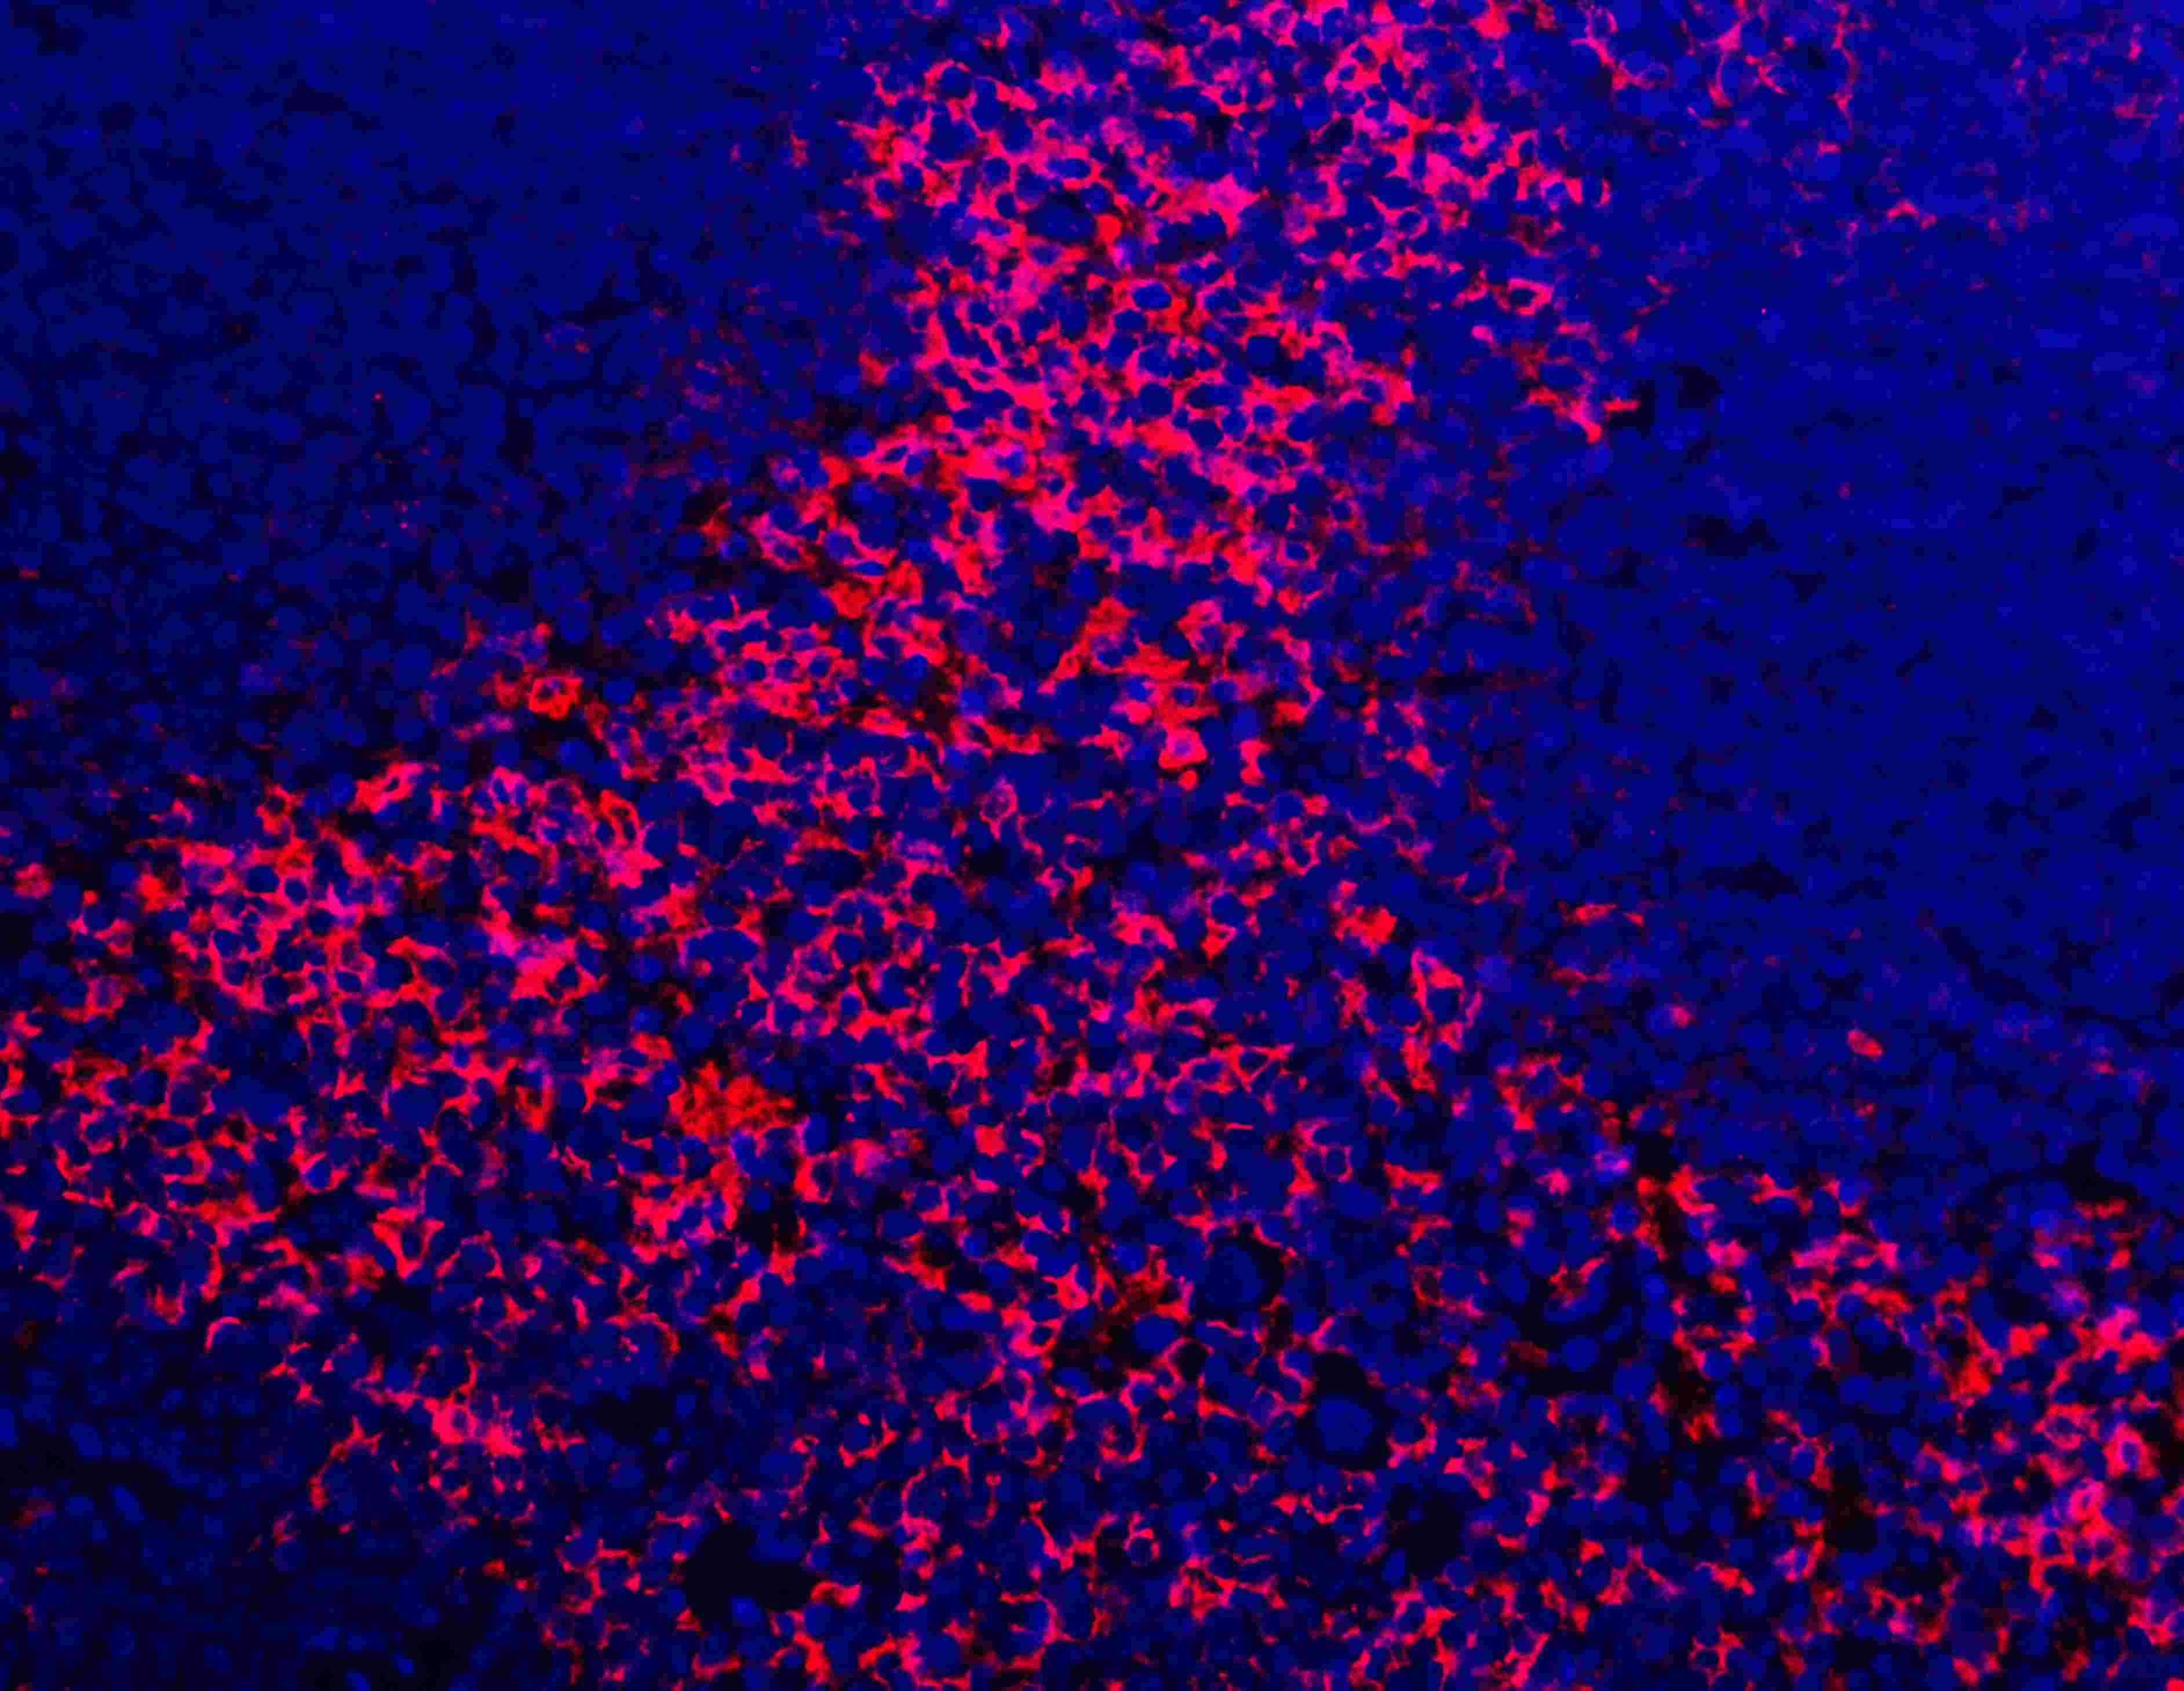

IF analysis of F4/80/Adgre1 using anti-F4/80/Adgre1 antibody (A08751).

F4/80/Adgre1 was detected in a paraffin-embedded section of mouse spleen tissue. Fluoro550-conjugated Anti-rabbit IgG Secondary Antibody (red)(Catalog#BA1135) was used as secondary antibody. The section was counterstained with DAPI (Catalog # AR1176) (Blue).